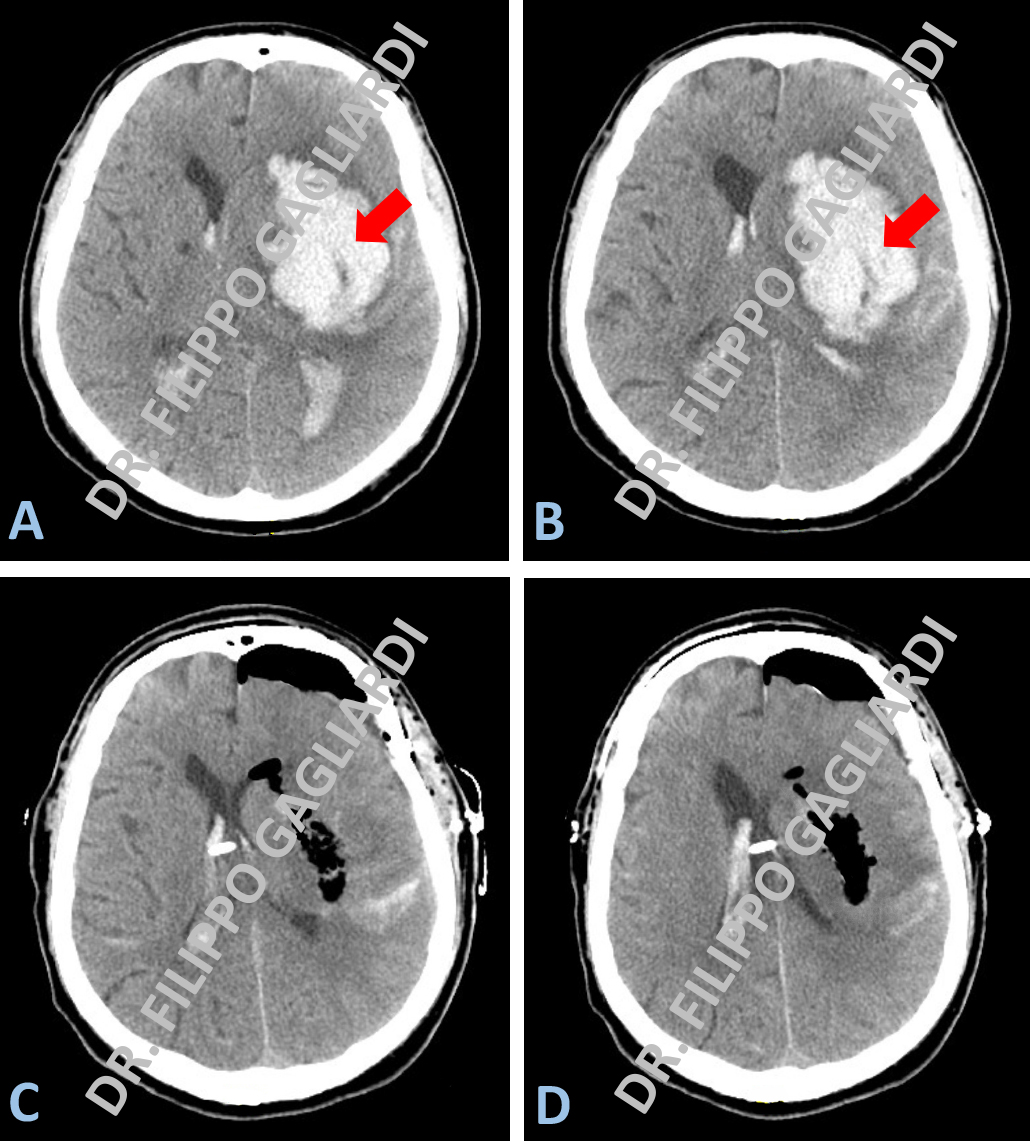

Emorragie cerebrali Tra le emorragie cerebrali, questo è un caso di emorragia spontanea profonda a livello dell’emisfero cerebrale di sinistra. Le Figure A e B mostrano la TC encefalo prima dell’intervento, eseguito in regime di emergenza. Qui si apprezza un’area iper-densa (bianca) corrispondente all’ematoma che esercita un effetto compressivo sulla parte di cervello sano dislocandolo dalla parte opposta. Il paziente è stato operato mediante tecnica mini-invasiva trans-corticale con l’utilizzo di un neuroport (piccolo divaricatore tubulare) con evacuazione completa dell’ematoma. Le Figure C e D mostrano gli esiti dell’evacuazione chirurgica dell'emorragia, con la scomparsa dell’immagine riferibile all’ematoma e la presenza di un catetere di derivazione all’interno delle cavità ventricolari per il monitoraggio della pressione intra-cranica.